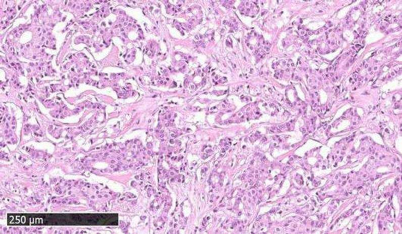

Clinical data. We used experimental data obtained during observational clinical investigation NCT03521245 “Molecular pathway activation markers predicting efficacy of trastuzumab therapy for HER2-positive breast cancer”. The patients were residents of north-western and central parts of the Russian Federation who underwent treatment in Vitamed Oncological Clinic, Moscow, or in Oncological Dispensary of Karelia Republic, Petrozavodsk, Russia. The inclusion criteria were: adult females with histologically confirmed HER2 positive breast cancer and available formalin fixed paraffin embedded (FFPE) samples of BC tissue; patients treated with Trastuzumab alone or in combination(s) with other chemotherapy regimens with known outcome according to RECIST 1.1; patients with BC stage II or higher who have signed an informed consent to participate in this clinical trial. The exclusion criterion was presence of less than 70% of intact tumor cells in the available FFPE BC tissue samples (Fig. 1). Totally, 23 patients were enrolled, and the respective tumor tissue specimens were profiled by RNA sequencing (Table S1 in the Supplement). The mean age of the patients was 53.3 years. The tumor response criteria used was remission for 25 months since the biopsy. The patients were then classified accordingly as either responders or non-responders to treatment with trastuzumab containing therapies. However, we could not directly compare trastuzumab response statuses for all the patients included because they had different types of HER2+ breast cancer (HER2+ luminal B type, or HER2+ ER–/PR– type). These two types of BC have different prognosis [25, 26] and it seems inadequate to compare them directly. For further analysis we selected a cohort of patients who received adjuvant therapy, had ER/PR-negative BC, and had metastases; in total five treatment responders and four non-responders were selected. All patients received trastuzumab in various combinations. The most common combinations included taxanes (paclitaxel or docetaxel, n = 7) and doxorubicin (n = 6, Table 1).

Fig. 1. Representative histological image of breast cancer tissue under investigation. Microphotograph of hematoxylin and eosin stained sample showed moderately differentiated infiltrative ductal cancer (BC71 HER2+/ER–/PR–).